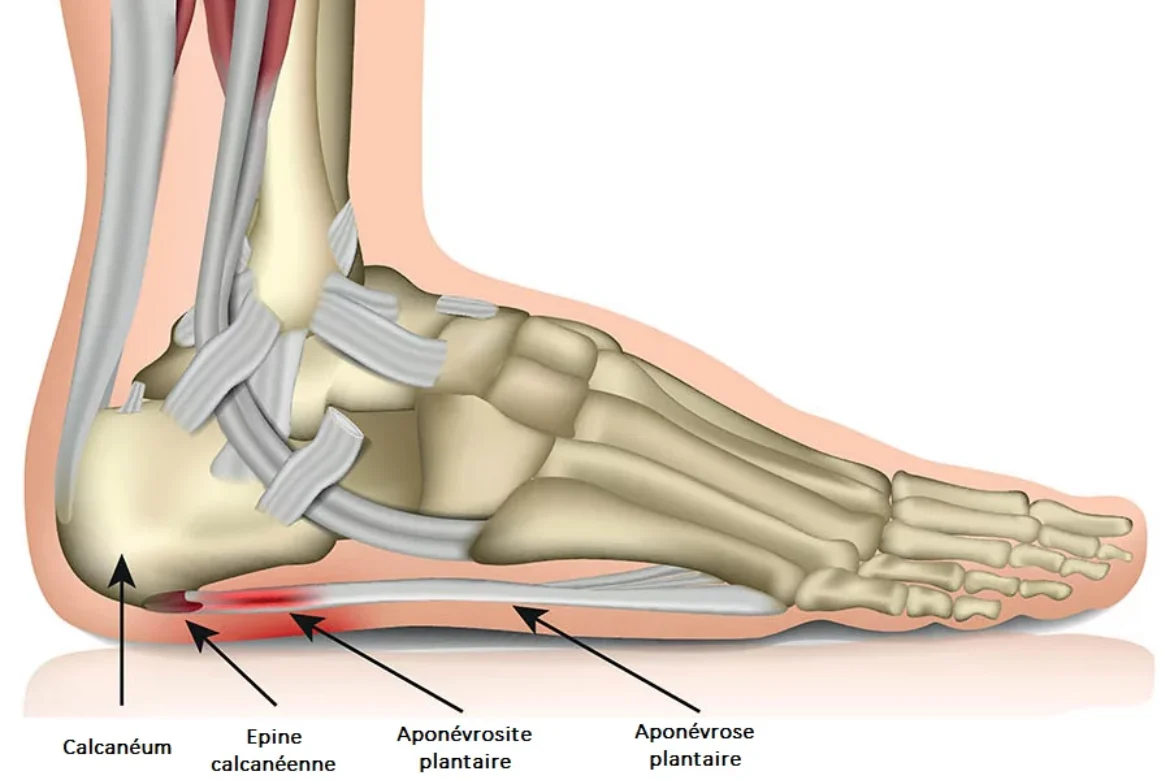

plantar-fasciitis-illustration-511e79

L’APONEVROSITE PLANTAIRE (EPINE CALCANEENNE)

En savoir plus